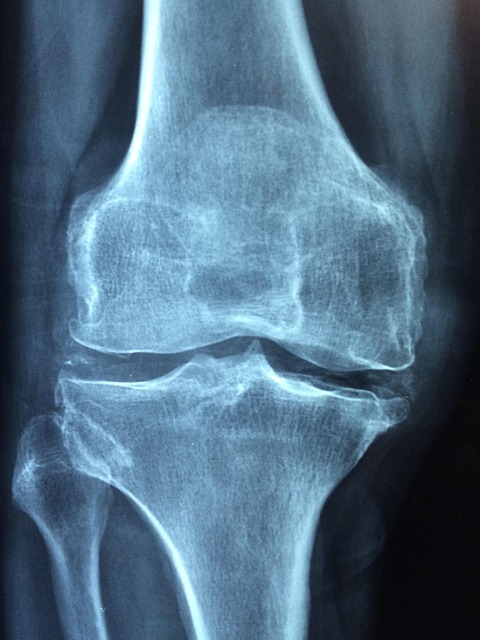

검사는 주로 골밀도(DXA, DexaScan) 검사로 이루어지며, 이는 X-레이를 통해 주요 뼈 부위의 밀도를 평가합니다. 이를 통해 개인의 골밀도가 정상, 낮음, 혹은 골다공증 상태인지를 판별할 수 있습니다. 이러한 정보는 적절한 치료 및 예방 계획을 세우는 데 필수적입니다.

골다공증 검사는 뼈의 밀도를 측정하여 뼈가 얼마나 약해져 있는지를 진단하는 중요한 과정입니다. 대표적인 골다공증 검사 방법으로는 이중 에너지 X선 흡수법(DXA 듀얼에너지 X-레이 흡수법), 초음파 검사, 그리고 CT스캔이 있습니다.

먼저, 이중 에너지 X선 흡수법(DXA)는 가장 널리 사용되는 골밀도 검사로, 일반적으로 척추와 고관절의 밀도를 측정합니다. 이 방법은 비교적 정확하고, 방사선 노출이 낮기 때문에 안전하게 사용할 수 있는 검사 방식입니다.